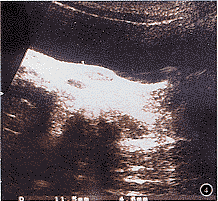

例1 患者2岁。因阴道淋漓出血2个月余,发现阴道肿物1个月,于1996年12月10日转来我院就诊。检查:阴道口内可见一紫色肿物,有恶臭。肛门检查可触及阴道内肿物,直径约4~5 cm,不规则,边界尚清,易碎,易出血。盆腹腔B超显示:子宫3.8 cm×2.5 cm×1.8 cm,阴道内可见一3.0 cm×2.9 cm×2.3 cm中等回声区,边界不清(图1)。双侧卵巢、肝、胆及双侧肾均未见异常。胸部X线片未见明显病变。血清甲胎蛋白(α-FP) 15 100 μg/L,hCG<10 IU/L。阴道肿物活检,病理诊断为:内胚窦瘤(图2),免疫组化染色,α-FP(++),癌胚抗原(-),β-hCG(-)。首先采用顺铂、长春新碱、博莱霉素(PVB)方案化疗3个疗程(长春新碱1.5 mg/m2,第1~2天;顺铂20 mg/m2,第1~5天;博莱霉素18~20 mg/m2,第2天;每周注射1次)。之后考虑博莱霉素的肺纤维化毒副作用,改用鬼臼乙叉甙替换博莱霉素,即PVE方案(长春新碱1.5 mg/m2,第1~2天;顺铂20 mg/m2,第1~5天,鬼臼乙叉甙100 mg/m2,第1~5天)治疗4个疗程。阴道内胚窦瘤对该化疗方案很敏感,血清α-FP每个疗程呈对数下降,第3个疗程后下降至正常范围,此后一直维持在低水平(图3)。第4个疗程后复查阴道B超,阴道内占位性病变消失(图4)。第7疗程后,在麻醉下行阴道检查,阴道内未见明确肿物,阴道后壁有数个小黄点,取黄点组织行病理检查,结果为少量鳞状上皮及纤维结缔组织,未见癌细胞。此后,又交替使用长春新碱、更生霉素、环磷酰胺(VAC方案)和PVE方案各1个疗程,以巩固化疗。该患者于1997年10月10日停用化疗,现在随诊中。无瘤生存已22个月。

图1 盆腔B超显示,阴道内可见3.0 cm×2.9 cm×2.3 cm中等回声区,边界不清

图4 PVB化疗4个疗程后,盆腔B超显示,阴道内占位性病变消失